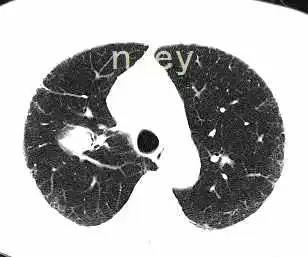

肺实变x线表现图片,肺不张x线表现图片

1 患者肺部影像学变化

胸部x线显示双侧气胸(左>右),右叶有薄壁空洞.

平片和ct:空洞是肺实变,肿块或者结节内的充气空隙,呈现透亮区或者低